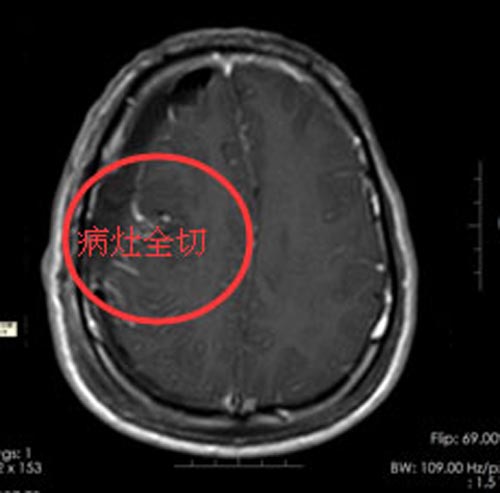

由综合神经外科鲁明副院长主刀在唤醒麻醉下行“左侧占位病变切除术+癫痫灶切除术”。手术中秦先生被唤醒,通过肢体活动以及和医生交流谈话,结合电生理结果,准确定位肿瘤,保护好功能区,完整地切除了病灶。

术后,秦先生恢复很好,影像检查证实肿瘤得以全部切除,不仅抽搐症状完全消失,而且没有出现失语、偏瘫等后遗症。